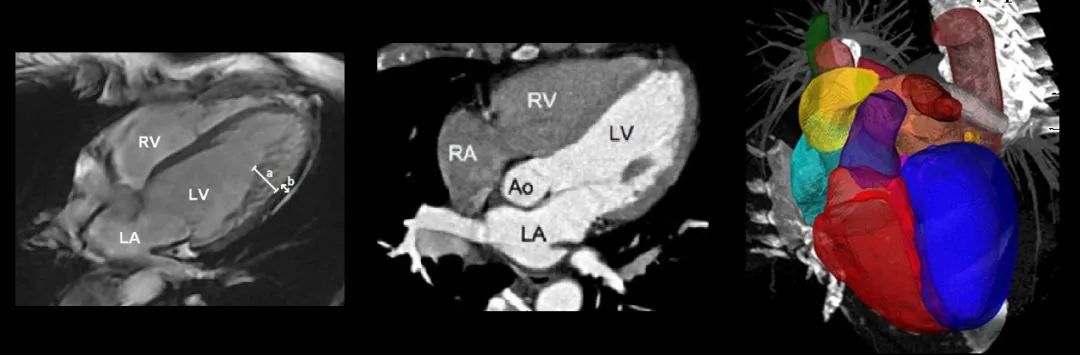

在心脏分割问题中,通常按结构将心脏分成几个标注区域。比如以MM-WHS数据库为例,有:

• 左心室血腔(the left ventricle blood cavity, LV)

• 左心室心肌(the myocardium of the left ventricle, Myo)

• 右心室血腔(the right ventricle blood cavity, RV)

• 左心房血腔(the left atrium blood cavity, LA)

• 右心房血腔(te right atrium blood cavity, RA)

• 升主动脉(the ascending aorta, AA)

• 肺动脉(the pulmonary artery, PA)

2. 完整心脏分割

基于P3D和FPN实现完整的心脏分割:

Zhanwei X., Ziyi W., and Jianjiang F.. CFUN: Combining Faster R-CNN and U-net Network for Efficient Whole Heart Segmentation[C]. CVPR 2018.